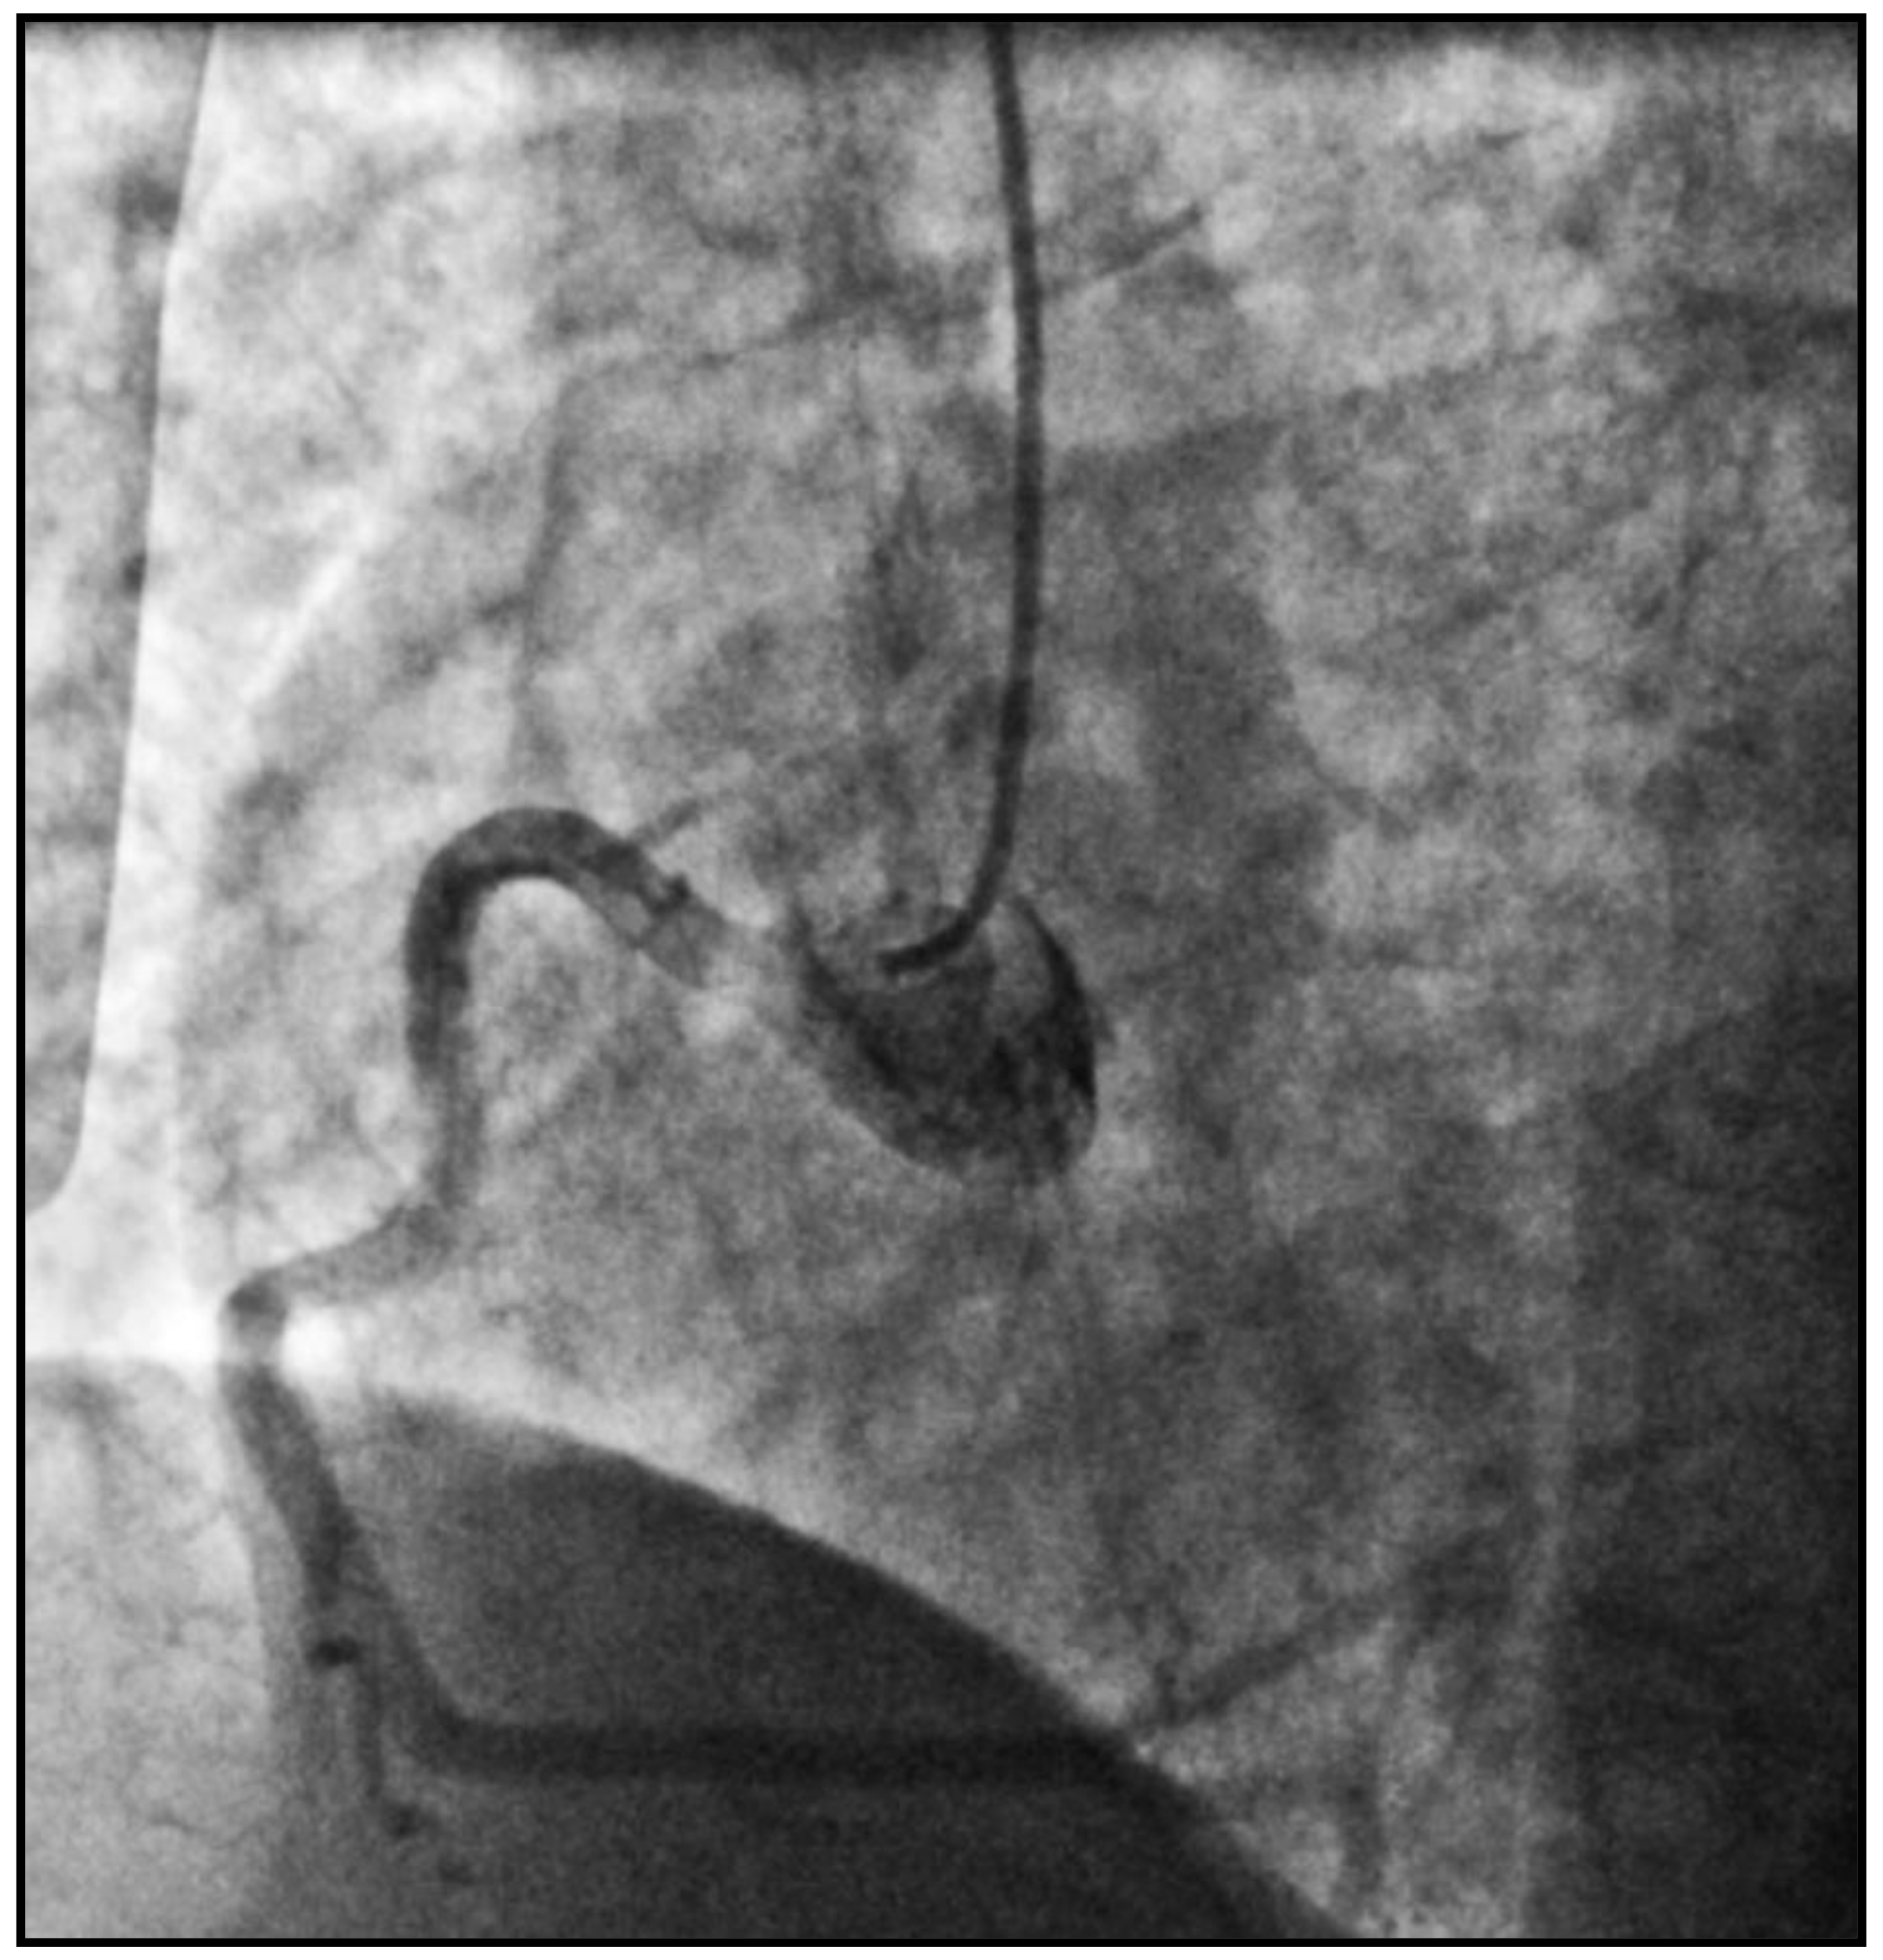

She was immediately transferred to cath lab from CCU, and an emergent coronary angiography was performed by intubating a right coronary artery (RCA), with the 6F diagnostic catheter showing a dominant high-caliber vessel giving off posterolateral (PL) and posterodescending (PD) branches with normal TIMI-3 flow and no signs of obstructive coronary disease (Figure 1).

Figure 1. A coronary angiogram of the right coronary artery (RCA).